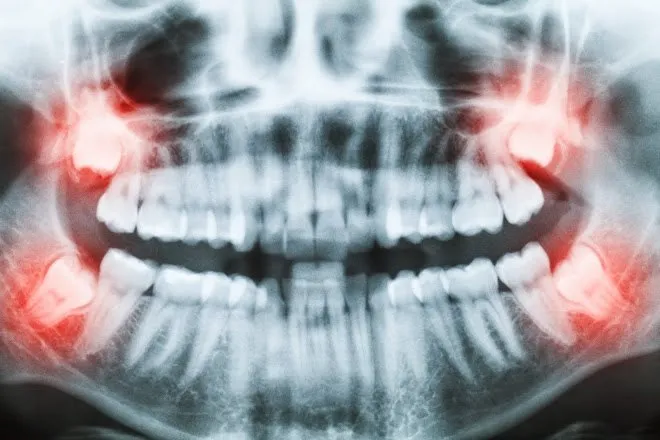

3. Há Inigualáveis "Sisos Muito Mais Complicados"

Toda anatomia esquelética difere! Nunca encare extrações alinhadas as promessas curtas do vizinho como modelo real:

- Os Sisos Simples Padrões: Erguem-se verticais iguais a dentes normais já furando sua gengiva para fora com fácil extração simples de tenaz em dois rápidos minutos inteiros.

- Os Sisos Horizontais Ocultos (Impactados Terceiro Molar): Totalmente "deitados" trancafiados pela espessa cortical óssea, repousando por baixo empurrando raízes mortais dos molares do meio. Nossos cortes demandam longos minutos de blocos secionados, separando delicada raiz por raiz por conta de cruzarem veias maxilares mandibulares nevrálgicas de dor (Eles criam um resguardo forte roxo com restrições difíceis de abrir a fala nos dias de trás).

- Se a imagem da Tomografia revela raízes do terceiro dente completamente alinhadas sem tranco para fora empurrar;